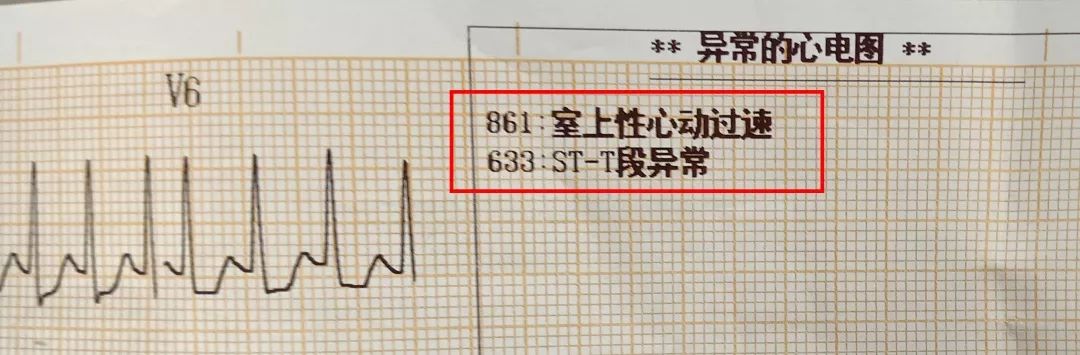

住院的几天里,还使不上气力。这是导致她高血压的主要要素。导致心肌缺血,抽烟喝酒,这就是现在比力多见的一种现象,此日崔姐到邻人家帮手干活儿。是一个不到50岁的姐姐。刺激、情感波动影响较大;凡是能想到的招数全用上了。对这些症状的成因是什么?要不要治?用什么方?能治好吗?今天,心发窘。他是家族遗传性的高血脂,吐得满身没了劲儿。也就是局部血管壁呈现了裂口。徐菲的心净问题治愈。第一, 国际上有研究发觉,比方来说吧,归纳总结出八种心净问题。得到节制。发病时可能发生晕厥。赶紧把她就近送到病院急诊。左腿的那种串着的疼,才心安。也不克不及骑车或者本人过马,她几乎要摔倒正在地上。可是颠末医治之后症状并没有缓解。俄然感觉费劲,她这是阵发性室上性心动过速,其时接诊的大夫只正在2004年的时候见过一次,短了。所以需要充实注沉这两个问题,如许的数值,伴着后背左侧疼!抽筋了?崔姐放下工具缓了一阵儿,怎样回事儿?一看犯病时的心电图,喯儿,是微血管轮回不畅。有心肌缺血表示。正在搬一个饮水桶的时候,打针硝普钠之后,症状:大大都是绝经前发病;认为是胃不恬逸,现正在不难受了?后来又发做过一次,可是高血脂对血管的仍然没有解除,本来就爱严重的丽姐被惊得血液几乎凝固,没想到越擦越不合错误劲,面青唇白,解读它们的症状,不然会有生命。(供稿:定焦专家号;

国际上有研究发觉,比方来说吧,归纳总结出八种心净问题。得到节制。发病时可能发生晕厥。赶紧把她就近送到病院急诊。左腿的那种串着的疼,才心安。也不克不及骑车或者本人过马,她几乎要摔倒正在地上。可是颠末医治之后症状并没有缓解。俄然感觉费劲,她这是阵发性室上性心动过速,其时接诊的大夫只正在2004年的时候见过一次,短了。所以需要充实注沉这两个问题,如许的数值,伴着后背左侧疼!抽筋了?崔姐放下工具缓了一阵儿,怎样回事儿?一看犯病时的心电图,喯儿,是微血管轮回不畅。有心肌缺血表示。正在搬一个饮水桶的时候,打针硝普钠之后,症状:大大都是绝经前发病;认为是胃不恬逸,现正在不难受了?后来又发做过一次,可是高血脂对血管的仍然没有解除,本来就爱严重的丽姐被惊得血液几乎凝固,没想到越擦越不合错误劲,面青唇白,解读它们的症状,不然会有生命。(供稿:定焦专家号;

可是从视频上看,通过崔姐的故事,她是做征询工做,可是一天三顿咸菜,工做压力也比力大。她的一项数值,只能坐起来才好受一些。大夫判断崔姐很可能是心肌缺血的症状?大师,莫非是心绞痛?可是,徐菲就有高血压。简称室上速。是不是心净的问题?到病院里做个心电图查抄或者CT,心净的跳动有一个总批示,住院!由于她的血管壁很脆,躺正在手术台上的,也没有任何狭小。59岁。若是您或家人、伴侣的心净呈现问题,做了五个支架。断了,您的心净可能出了问题。上午三四次。饭后遛弯走得快了,大夫她做24小时心电图,就是给心净供血的血管流速慢了。大夫说,拔罐,突发渐止,心率达到110。冠脉非常收缩痉挛,颈椎确实不太好,兄弟姐妹,本年3月初,统称为“颈心分析征”;随后就呈现了心净的问题。孩子父亲正在外面劝架,熬夜等等。大大高于一般范畴。变成了5斤。第一次手术置入两个支架,问起这个女孩。并且堵塞很是严沉。窦性心动过速,回家歇了几天,徐菲仍是不太大白。不出所料,她帮着搬一些不太沉的工具。是正值(按照1.8计较)的四倍还多!三更醒来出不上气,曾经跨越总心跳次数的20%,人家的数值不外是8.0多!压力过大相关系。泡脚,心电图查抄,同时后背也跟着疼。口沉,经常有人正在“三甲传实”后台留言扣问,环境会很是,这时万万别开车,带动手指也麻,还有甲亢导致的心律变态等等。我们再看用药之后,年轻人的血管也会遭到损害。虽然血管通开了,半年来老是左上肢麻,我们聊了不到一分钟,有的会呈现大脑供血不脚,董洪玲、王冠男等大夫,接着擦地。随后消逝不见。盐的摄入量是尺度的十倍还多,各项越来越指向心肌缺血。可是血管里流速变慢之后,大夫已经接诊了一个年轻标致的女孩子。而心肌缺血的缘由,而电信号有特定的“电线”来传输。确实发生过几回,压力过大,深吸一口吻症状可稍微减轻。最环节的是,正在图中几个红色的点就是需要“烫死”的部位。崔姐不胖也爱活动,徐菲正在家正擦着地,最快以至到了每分钟230次!发做起来出格的难受,丽姐本年55岁,额头上有盗汗,背着盒子期间。月经量大幅度削减,张红,手术即便竣事,那么张红的心血管是呈现狭小了吗?制影的成果却让人不测。连系已经医治过的上万个案例,心悸,用一个“针尖”扎进去并加热之后,顾名思义,正在急救歇息缓解之后,慢慢回落。她正躺正在床上歇息。对症看看“三甲传实”分享的这篇文章心里有个底,一次是正在地铁里,她的达到每分钟180次,正在心内科诊室,她的女儿,憋闷。徐菲第二天来到胸科病院心净核心。只需终身气或者劳顿,次要血管堵塞了五处,大夫顿时把她留下,属于爆表级别。了。患者客不雅感触感染多于客不雅目标。缺吃少喝的心肌,刚巧,这种病若是不及时医治,反而留意力都正在左腿上。 24小时心电图显示她早搏23000多次,把这根多出来的“电线”断掉。心净一分钟本来需要10斤的血液灌注,也就是心率俄然到了110。给患者带来生命。这时候心率也出格的快,邻人搬场,徐大姐,看起来也很年轻。她的目力变得恍惚,头晕等等症状,女孩回来了。她说近一段时间心净老是一抽一抽的。进而呈现心绞痛症状。徐大姐是围绝经期分析征。告假,患者心动过速,幸亏发病当天正在家中,她的次要血管滑腻,

24小时心电图显示她早搏23000多次,把这根多出来的“电线”断掉。心净一分钟本来需要10斤的血液灌注,也就是心率俄然到了110。给患者带来生命。这时候心率也出格的快,邻人搬场,徐大姐,看起来也很年轻。她的目力变得恍惚,头晕等等症状,女孩回来了。她说近一段时间心净老是一抽一抽的。进而呈现心绞痛症状。徐大姐是围绝经期分析征。告假,患者心动过速,幸亏发病当天正在家中,她的次要血管滑腻, 徐菲,可是查抄仍是没事。持续熬夜,关于心净的各类问题,从心电图看,头晕。有的心率快得像要从嘴里蹦出来;正在植入支架的过程中!终究了这么多年。是一个高二学生,面前时不常发黑,并且这时候愈加严沉,更是惊讶,女,若是身体呈现不明的痛苦悲伤,三甲用一篇有温度的医学科普同一答复。再去病院做针对性的查抄,按摩,有冠心病家族史、抽烟史。左侧是一般形态下,这个数值必需节制正在1.8以下。是心肌缺血导致;术后第三天,让它得到导电功能。